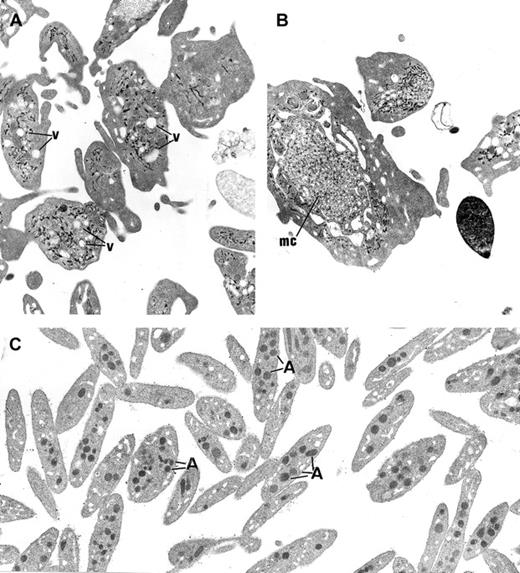

Electron microscopy of platelets and MKs

The platelets from the 3 children displayed similar ultrastructure. Platelet size was heterogeneous, and many platelets were larger than a red blood cell or a small lymphocyte. The most striking morphologic abnormality was the lack of normal α-granules and prominent vacuolization of the cytoplasm (Figure3A). Membrane complexes, which represent abnormally distributed intracellular membrane, were also observed (Figure 3B).

Ultrastructure of platelets.

(A) In GPS, normal α-granules are absent from the platelets and replaced by vacuolar structures (v) the size of normal α-granules. (B) Platelets of large size displaying membrane complex (mc) and devoid of normal α-granules are encountered. (C) Platelets from a normal subject are smaller and display conspicuous α-granules (A). (Panels A-C, original magnification × 10 500.)